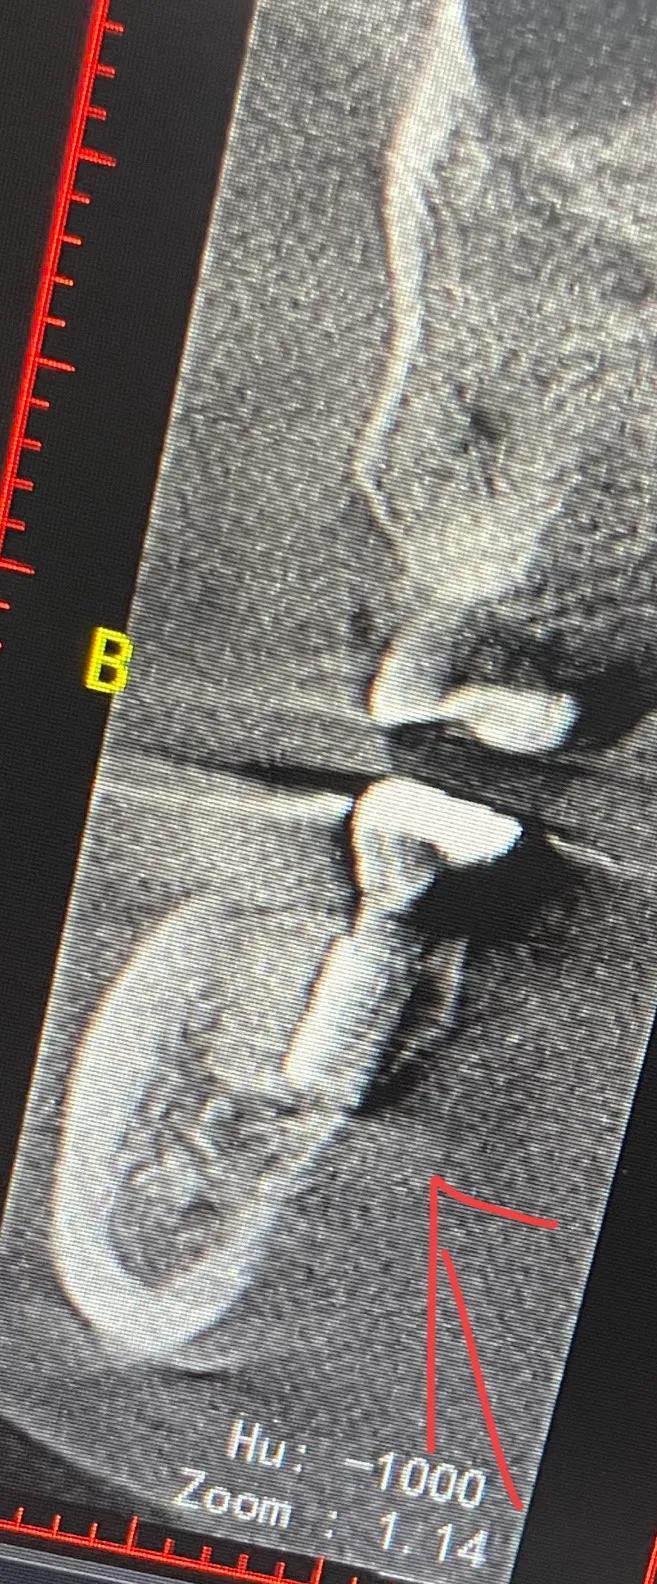

幾天后醫(yī)生?說把牙冠拿下來從新做 在那么劇烈的疼痛下 但凡醫(yī)生能早點(diǎn)?找一下原因 也不會遭這么大的罪 去其他醫(yī)院拍片子 說是?有骨頭高于種植體

戴上牙冠 多出來的骨頭在牙冠和種植體中間擠壓 所以會疼

沒辦法自己又出去拍片子 找原因 看了幾家醫(yī)院 才知道連種植體也種偏了 牙冠也沒有就位………